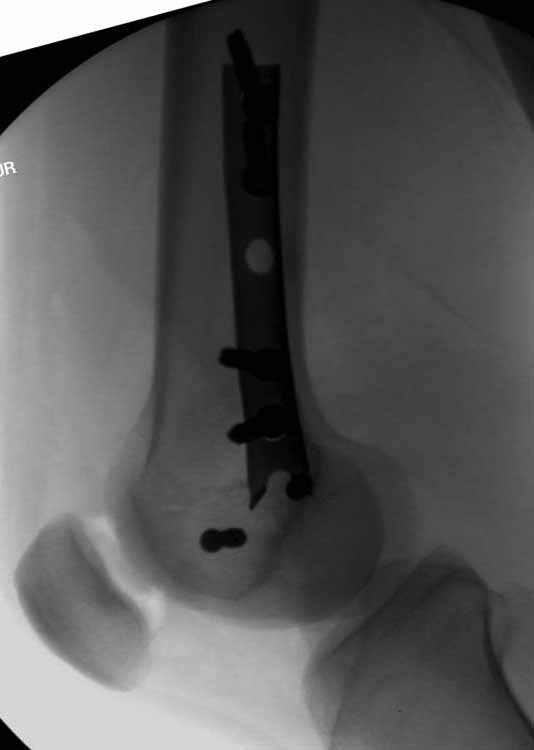

По снимку вроде одиночный простой мыщелковый перелом, и такой внутрисуставной перелом не обязательно дистрагировать на скелетном вытяжении, потому что не не нарушается непрерывность колонны с одной стороны. И для таких простых переломов подойдет любой метод: 95 градусная пластина, Lat. Condylar Butress пластина или ретроградный гвоздь. А для особых энтузиастов которые желают антеградную фиксацию, возможно легко найти трохантер у алкоголиков или дистрофиков. А вот у откормленных Макдональдскими гамбургерами? Если поискать у них тоже можно найти, но стоит ли?

У больных как в этом случае, с вовлечением двух мыщелков правильно, что сделали вытяжение до операции. Здесь имеется флексионный компонент на другой стороне, и я бы рекомендовал операцию делать из двух доступов. Сперва фиксировать медиальную колонну custom made пластиной, обычно 1/3 тубулярной пластиной в 4.5 мм, потому что пока производители опаздывают с медиальной пластиной.

Здесь пример медиальной пластины и латеральный комбинированный метод (у второго больного старый перелом тибиал плато, леченный где то и когда то)